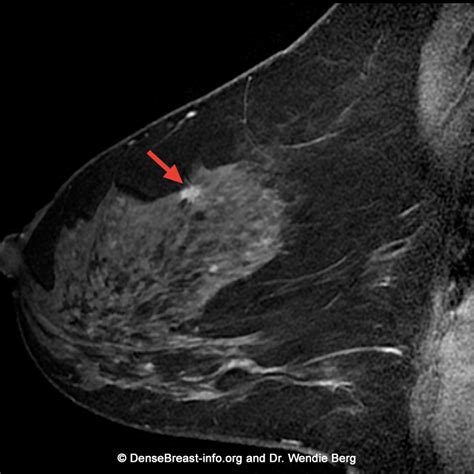

Once the MRI of breasts is complete, the images are sent to a radiologist who specializes in breast imaging. They will analyze the scans, looking for patterns of enhancement that suggest either benign or malignant tissue. It is important to remember that not every abnormality identified on an MRI requires surgery or a biopsy.

The radiologist will provide a report, often utilizing the BI-RADS (Breast Imaging-Reporting and Data System) scoring method:

- BI-RADS 0: Incomplete assessment; requires more imaging.

- BI-RADS 1 & 2: Negative or benign findings.

- BI-RADS 3: Probably benign, but short-term follow-up is recommended.

- BI-RADS 4 & 5: Suspicious abnormalities that may warrant a biopsy.

💡 Note: A BI-RADS 4 or 5 score does not automatically mean cancer; it means the tissue looks suspicious enough to warrant a tissue sample for a definitive diagnosis.

The integration of the MRI of breasts into the standard of care has drastically changed how we approach early detection. By offering a functional look at the tissue—observing how blood flows into a suspected mass—doctors can differentiate between healthy and suspicious structures with remarkable precision. This diagnostic power is a cornerstone of modern oncology, enabling personalized treatment plans and reducing the guesswork often associated with earlier diagnostic tools. While the process may feel daunting, the clarity provided by these detailed images is an invaluable asset in protecting long-term health.